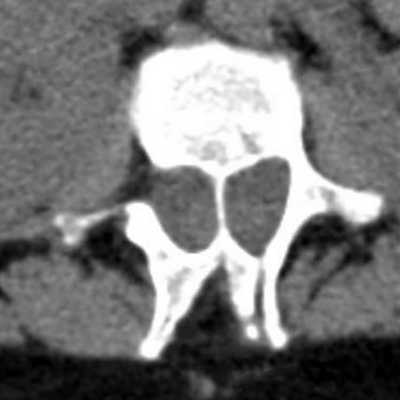

При диастематомиелии на компьютерной томографии позвоночника определяются расширенный позвоночный канал с разделяющей его костной перемычкой и расхождение краев костного дефекта дужки позвонка.